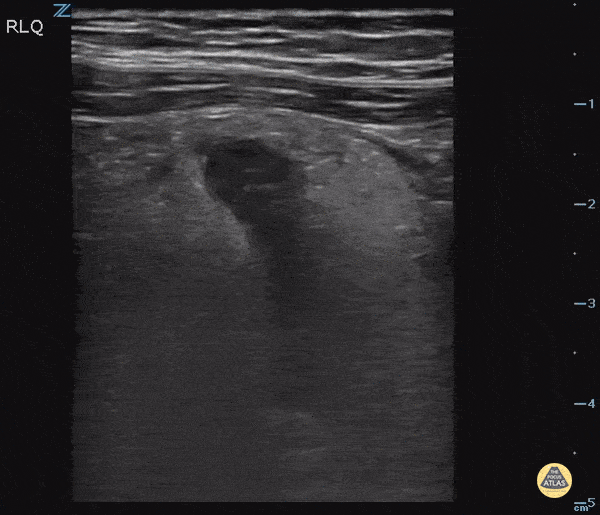

This image is from a patient presenting with right lower quadrant pain. It demonstrates findings of acute appendicitis including : a dilated fluid filled structure with thickened walls, surrounding hyperechoic fat (fat stranding) and an appendicolith. Check out our colorized image post on evaluating for acute appendicitis here. Image Courtesy of IUEM Ultrasound Original Twitter Post can be found here.